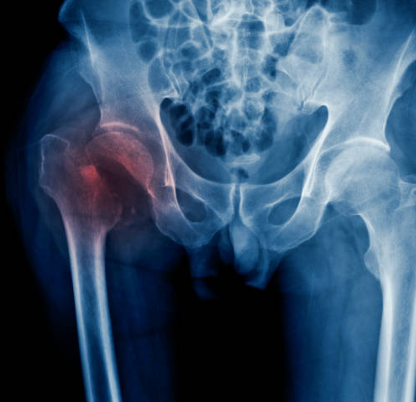

고관절 골절이란?

골다공증과 같은 뼈 약화 상태 또는 외상으로 인해 발생하는 대퇴골(허벅다리 뼈) 상단의 골절을 의미하는 것입니다. 일반적으로 낙상이나 직접적인 충격으로 인해 발생하며, 특히 고령자에서 흔히 일어날 수 있는 사고입니다. 고관절 골절치료는 주로 수술과 재활이 필요하며, 이는 환자의 이동과 삶의 질에 많은 영향을 미칠 수 있습니다.